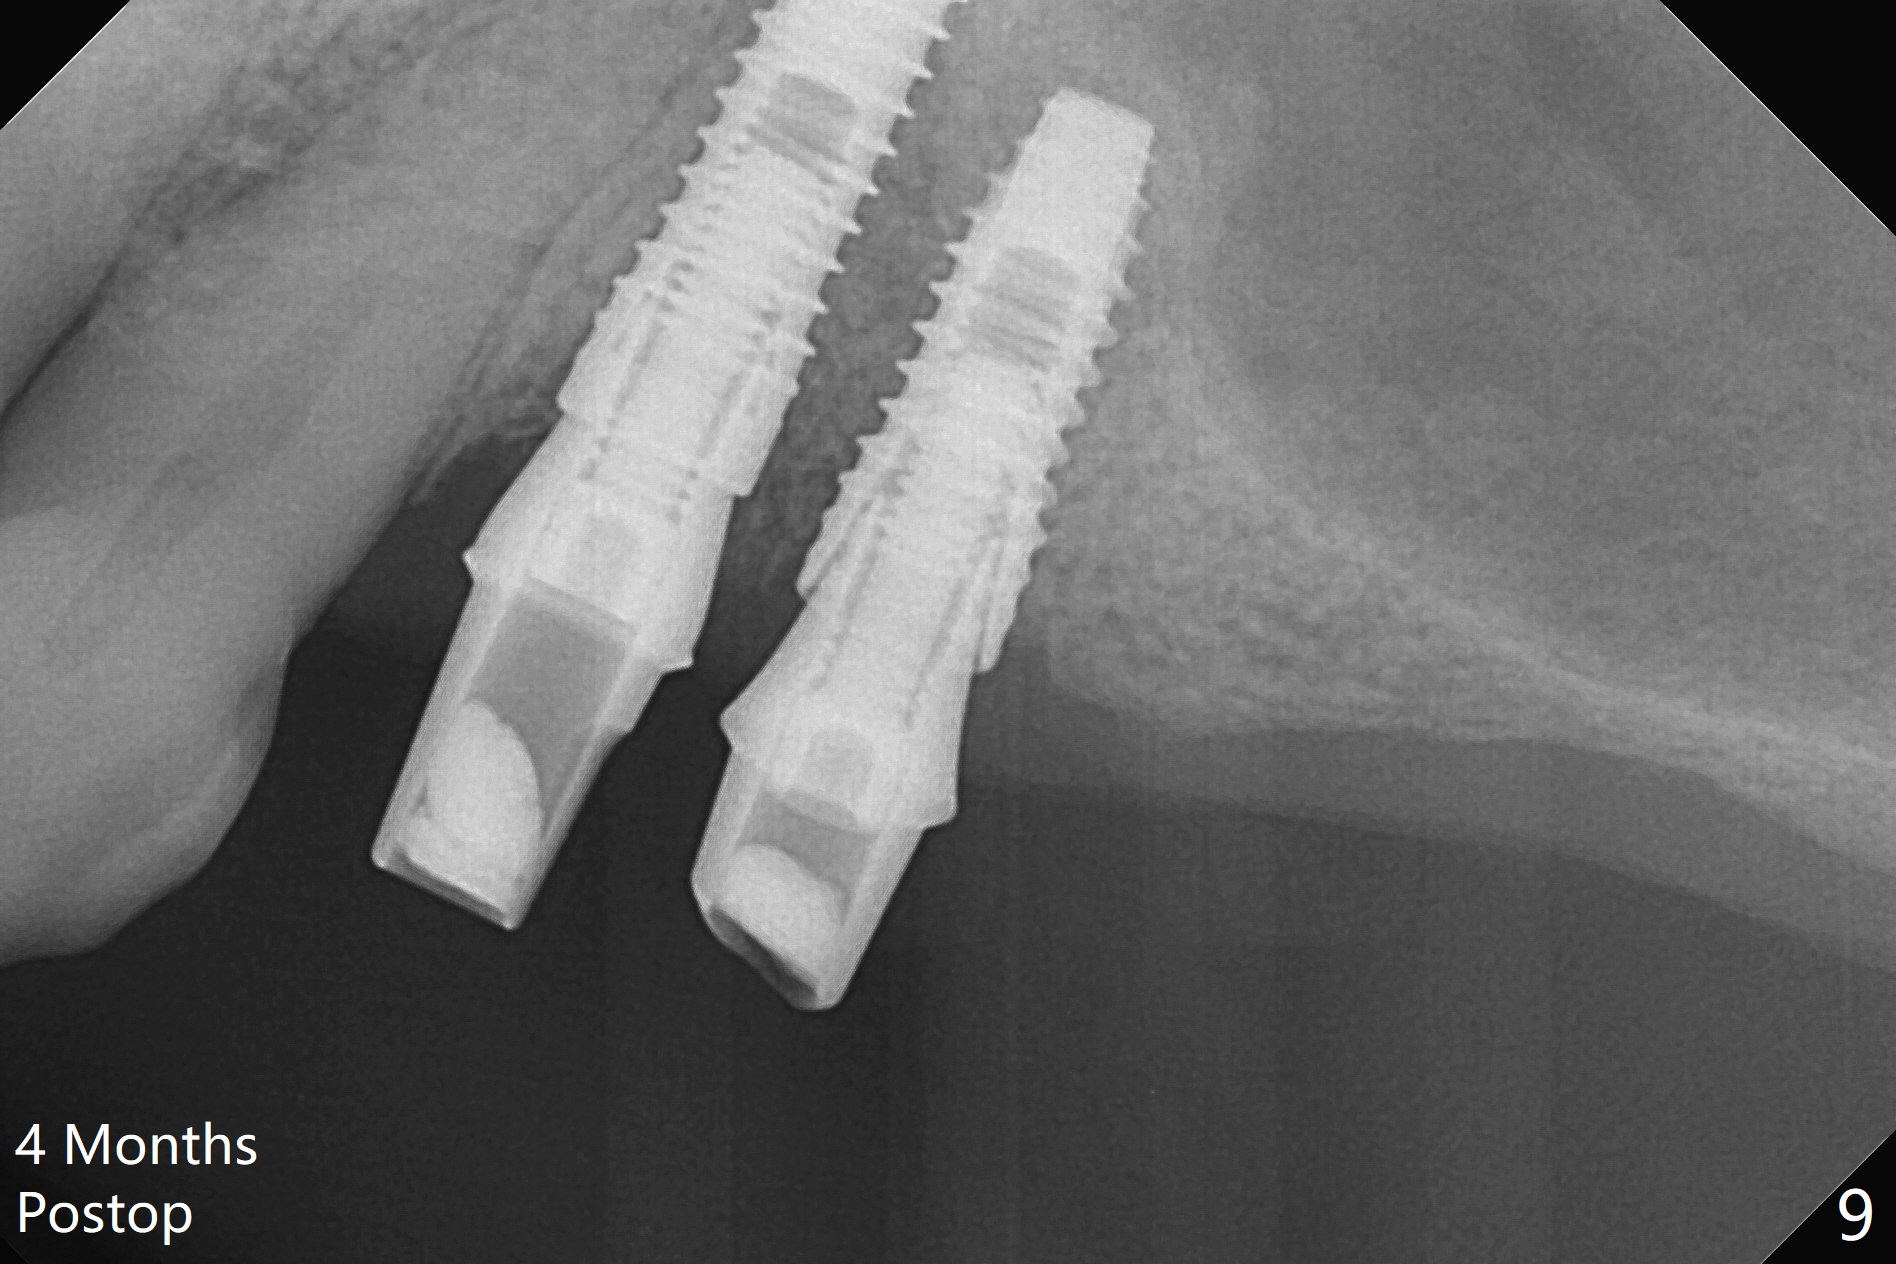

The buccal gingiva at #12 with vertical root fracture looks unhealthy (Fig.1). Osteotomy at #13 is initiated prior to #12 extraction. In fact the osteotomy happens in the extensive defect associated with #12 (Fig.2 red dashed line). To obtain primary stability, the osteotomy at #12 needs to be long, while that at #13 needs two-pointed fixation (Fig.3 *). After adjustment of trajectory at #12 and increase in diameter of the osteotomy at #13 (Fig.4), a 3.8x15 and 3.8x10 mm implants are placed (Fig.5). Following adjustment of implant depth (Fig.6), the implant at #12 becomes loose, while that at #13 tightens. With placement of abutments, an immediate splinted provisional is locked in place to stabilize the loose implant at #12 (Fig.7). The patient complains of cold sensitivity in the upper left quadrant, possibly related to the fact that the implant at #12 is close to the apex of the tooth #11. The position and trajectory of the initial osteotomies should be changed as shown in Fig.8 (white lines, as compared to Fig.2). There is no sensitivity 1 month postop. Impression is taken 4 months postop (Fig.9) after #13 mesiobuccal margin prep. The implants were placed too close to each other. The abutment screw at #13 is retightened 8 months post cementation. There appears no bone loss 9 months post cementation (Fig.10), while the tooth #11 has periapical infection with DL caries 1 year 7 months post cementation (Fig.11).